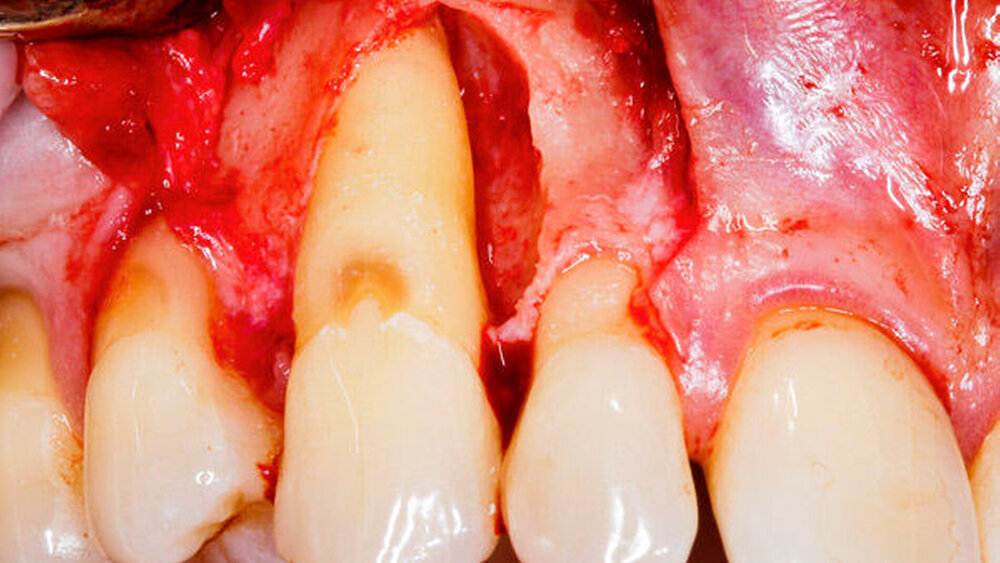

Trainieren Sie den Workflow im Team in einem praktischen Arbeitskurs. Halten Sie die zusammengebaute und korrekt eingestellte Kamera nebst Hilfsmitteln (Spiegel/Wangenhalter) griffbereit und integrieren Sie die Fotografie in Ihren Behandlungsablauf. So fotografieren Sie viel und gewinnen an Routine. Übung macht den Meister! Ziel ist die rasche Gewinnung von Bildern, die scharf, gut ausgeleuchtet und reproduzierbar sind. Achten Sie vor der Auslösung auf die Bildaufteilung – Wichtiges gehört ins Zentrum, Unwichtiges, beispielsweise die Nase des Patienten bei Palatinalaufnahmen von Frontzähnen, gehört an den Rand oder wird ganz weggelassen. Fotografieren Sie achsengerecht. Dies bedeutet, dass sich die optische Achse in der Okklusionsebene fortsetzt. Ein im Kamerasucher sichtbares Netzgitter (zuschaltbar bei manchen Kameramodellen) erleichtert die korrekte Ausrichtung der Kamera entsprechend den anatomischen Ebenen des Patienten. Zuletzt achten Sie auf die Bildkosmetik – Zahnstein und störende Zahnbeläge sollten vor der Aufnahme entfernt werden, falls sie nicht zum Bildinhalt gehören. Speichel sollte gut abgesaugt werden. Bei der Fotografie während operativer Eingriffe ist es wichtig, den Bereich möglichst blutfrei darzustellen.